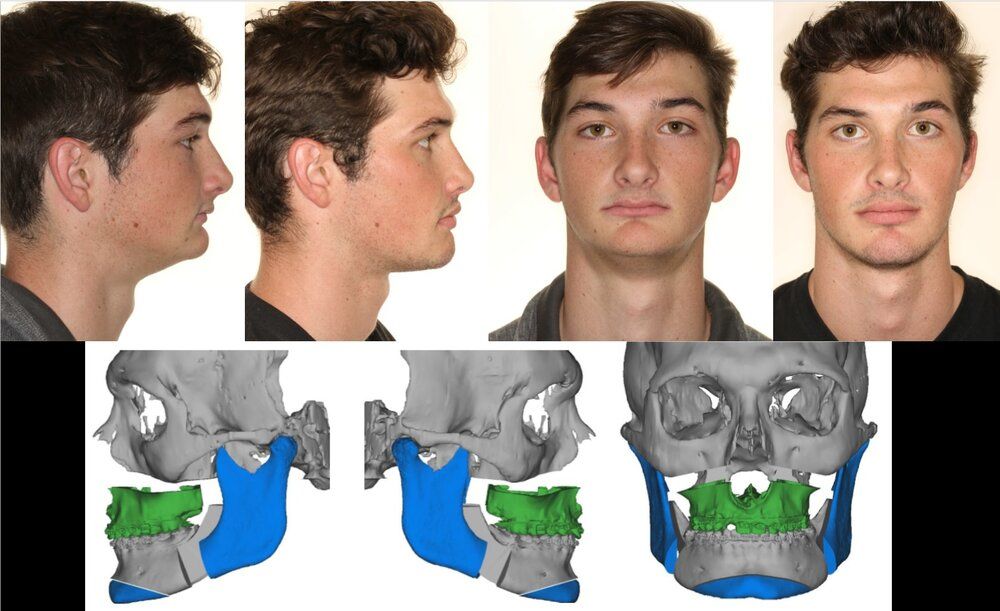

Important to note that my maxilla wasn’t downward grown until braces and headgear I am still 16 and upward thumb pressure is is not really doing anything much (I also had to fix my skeletal issue with my palate because my ortho only did tooth expansion instead of marpe/sarpe (aka breathing issues)